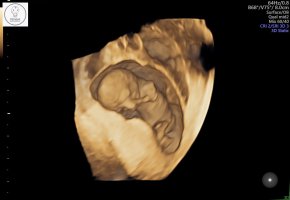

Her er vår lille krabat. Veldig aktiv og alt var helt perfekt❤️ Jordmor sa «denne er kommet for å bli», så det var gode nyheter. 12+2 i dag.